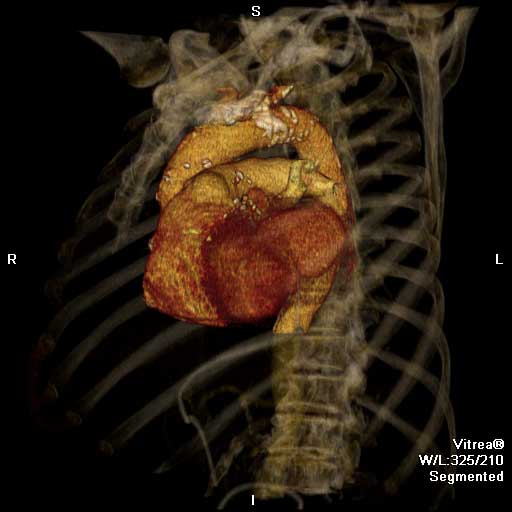

| Figure 1 & 2. Preoperative CT-scan | |

We report a case of a 78 y/o male with history of CAD, for which he underwent coronary artery by-pass surgery in 2004. The patient was admitted to the hospital with symptoms of moderate congestive heart failure. EKG showed no signs of acute ischemia and cardiac enzymes were negative. Cardiac ECHO showed a 6.8 x 5 cm pseudoaneurysm of the posterior left ventricle, well preserved ventricular function and no abnormalities of the mitral and aortic valves. Coronary angiogram demonstrated patency of all previous bypasses. The chest CT allowed better definition of the anatomy of the condition (Figure 1, 2). The procedure was performed through an antero-lateral left thoracotomy positioning the patient in a right lateral decubitus. The chest was entered at the 5th intercostal space and the sterno-costal junction was interrupted to optimize exposure. The left lung was displaced posteriorly and the pericardium was opened longitudinally and posteriorly to the phrenic nerve. Dissection of the heart surface from the pericardium was easily completed obtaining perfect exposure of the left ventricular pseudo-aneurysm. The previous by-pass grafts were never visualized, being distant from the operative field. Cardiopulmonary bypass was established through the left femoral vessels using a 17 F arterial femoral cannula and a 25 F multistage venous femoral cannula. The left ventricle was vented through the apex using a 10 F suction catheter. Systemic pressure was kept above 70 mmHg and the heart was decompressed before entering the left ventricular cavity via a longitudinal incision through the wall of the pseudoaneurysm (Figure 3). A bovine patch pericardial repair was completed with interrupted pledgetted sutures maintaining the architecture of the left ventricle (Figure 4). The closure was reinforced overlapping the wall of the pseudoaneurysm over the patch closure (Figure 5). Meticulous de-airing was completed under TTE monitoring before allowing ejection of the left ventricle into the circulation. De-airing was accomplished placing the patient in steep Trendelemburg position and maintaining full suction on the apical vent. Cardioplulmonary bypass was weaned-off without complications. The patient postoperative course was uncomplicated and he was discharged home in postoperative day 6. The postoperative CT-scan image is shown (Figure 6).